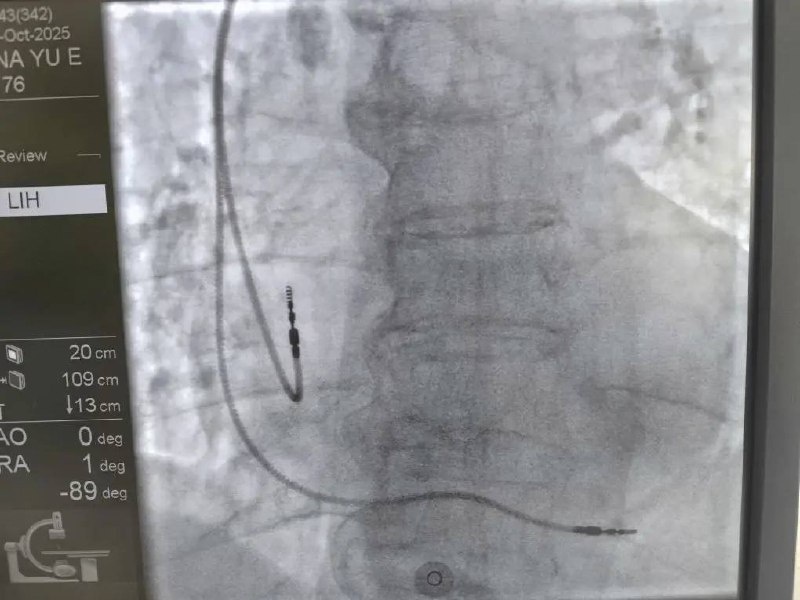

В Республиканской больнице впервые начали проводить операции по установке кардиостимуляторов. На регулярной основе в Республику будет приезжать сосудистый врач-хирург Илья Стенин с опытом работы в Национальном медицинском исследовательском центре имени академика Мешалкина. Чтобы не только проводить операции, но и обучать наших врачей. В первый день работы прооперированы пять пациентов. Также планируются консультации наших жителей, уже имеющих ЭКС, по вопросам их планового перепрограммирования. Раньше чтобы попасть на такую операцию, жители ездили в Барнаул или Новосибирск. Теперь такой необходимости нет - процедура доступна в Республике. Фото: Дмитрий Хубезов #новости 👍Подписывайся на Вести Эл Алтай МАКС | Телеграм

В Республиканской больнице впервые начали проводить операции по установке кардиостимуляторов.

На регулярной основе в Республику будет приезжать сосудистый врач-хирург Илья Стенин с опытом работы в Национальном медицинском исследовательском центре имени академика Мешалкина. Чтобы не только проводить операции, но и обучать наших врачей. В первый день работы прооперированы пять пациентов. Также планируются консультации наших жителей, уже имеющих ЭКС, по вопросам их планового перепрограммирования.

Раньше чтобы попасть на такую операцию, жители ездили в Барнаул или Новосибирск. Теперь такой необходимости нет - процедура доступна в Республике.

Фото: Дмитрий Хубезов